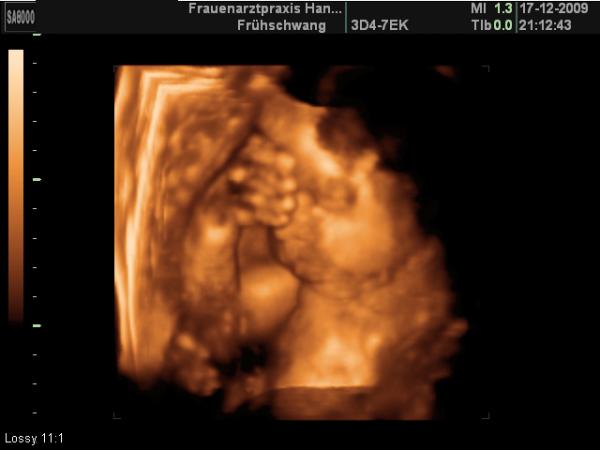

Süß ne?

Oh süss! Eine richtige Denkerin so mit der Hand an den Kopf gelegt... Süsses Bild!